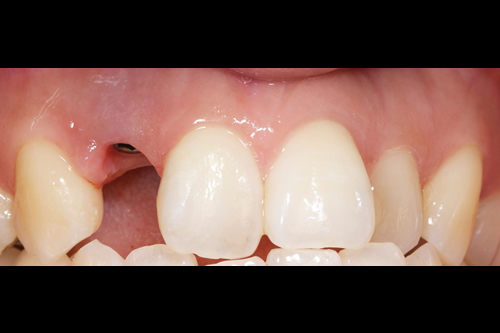

< 症例2 >

- 治療期間:8ヶ月

- 治療回数:12回

- 治療歯数:1歯

- 費用:インプラント治療:47万円 上部セラミック:89,000円

- リスク:メンテナンスを怠ると、インプラント周囲炎になる可能性があります。

- インプラント手術には合併症が伴う場合があります。

- 治療期間は治癒の状態により前後する場合があります。